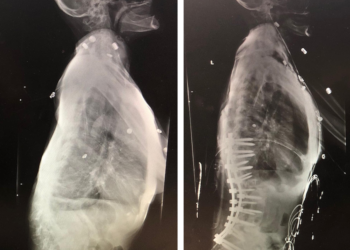

Spine:

Cervical Laminectomy and Fusion

Author: William Sonstein M.D., F.A.C.S., Read More!